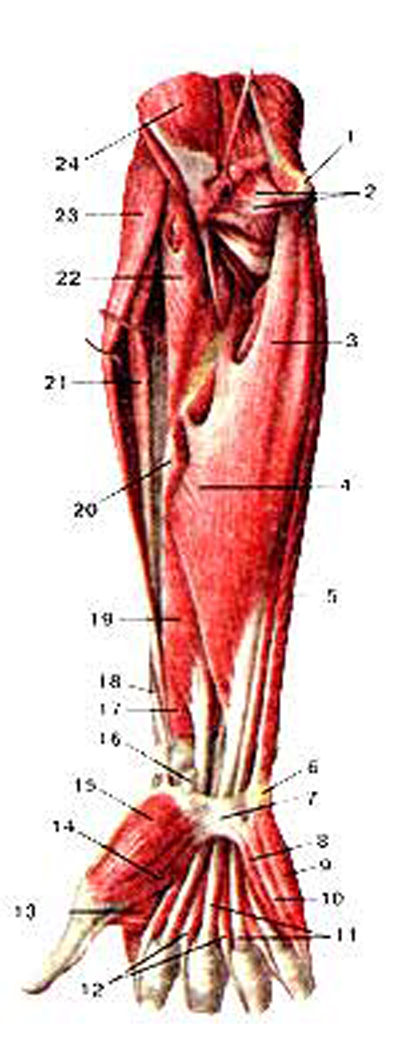

Анатомия мышцы Palmaris Longus